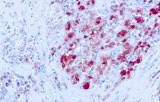

CE/IVD antibodies for immunohistochemistry (IHC) in neuropathology are validated in vitro diagnostic reagents used to detect specific neuronal and glial antigens in formalin-fixed paraffin-embedded (FFPE) tissue. Peer-reviewed neuropathology literature supports their role in improving reproducibility and diagnostic accuracy in central nervous system (CNS) diseases, including brain tumors and neurodegenerative disorders.

Targeted proteins such as GFAP, OLIG2, NeuN, synaptophysin, neurofilament, and Iba1 reflect astrocytic, oligodendroglial, neuronal, and microglial lineages. Their expression patterns are widely used in peer-reviewed studies to define CNS cell identity, differentiation state, and neuroinflammatory or degenerative processes.

CE/IVD IHC antibodies support CNS tumor classification (gliomas, embryonal tumors, metastases), assist in differential diagnosis, and help identify proteinopathies associated with Alzheimer’s disease and other neurodegenerative conditions. They are routinely used in biomarker panels for tumor grading and diagnostic stratification in neuro-oncology.